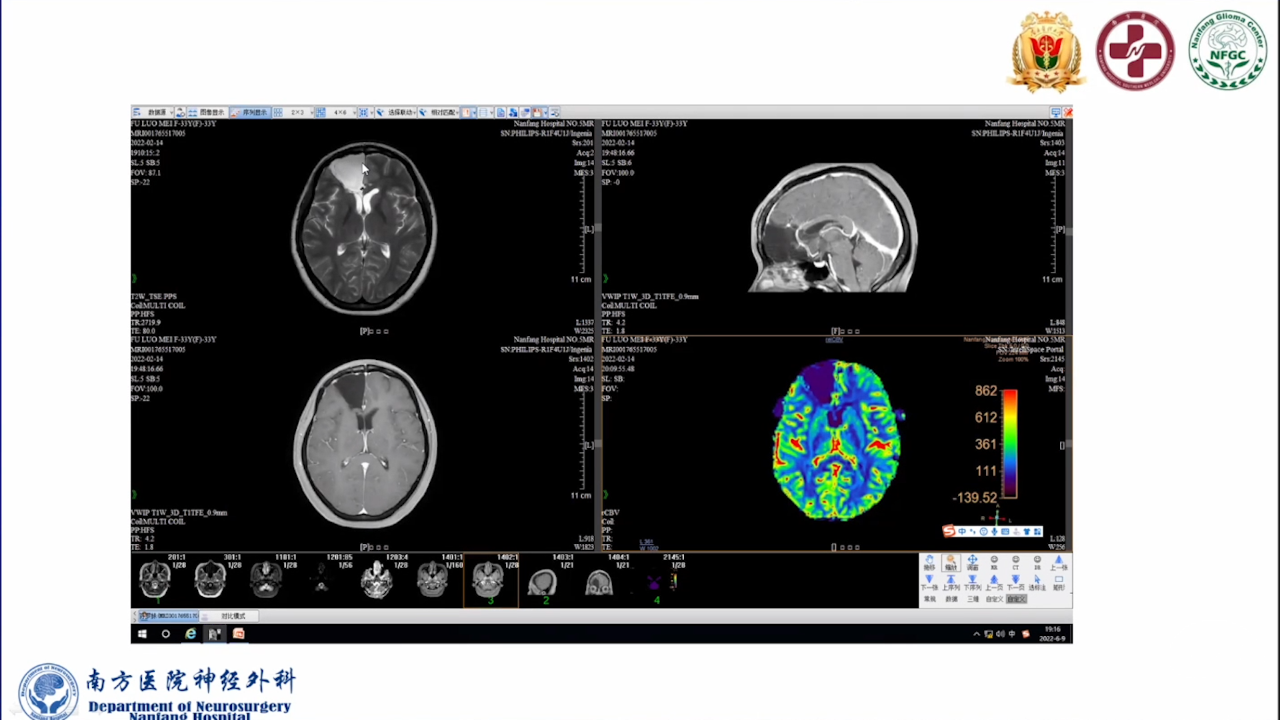

巨大的脑胶质瘤往往破坏皮层功能,推挤白质纤维束,包裹重要供血动脉,正常解剖结构移位。手术切除病变可以挽救患者生命。如果术中确保重要动脉不损伤,并在术前纤维束成像指导下按照解剖结构标志尽可能保留神经纤维束,患者将在获得辅助治疗机会的同时,神经功能也得以逐步恢复,更有利于脑胶质瘤的预后。